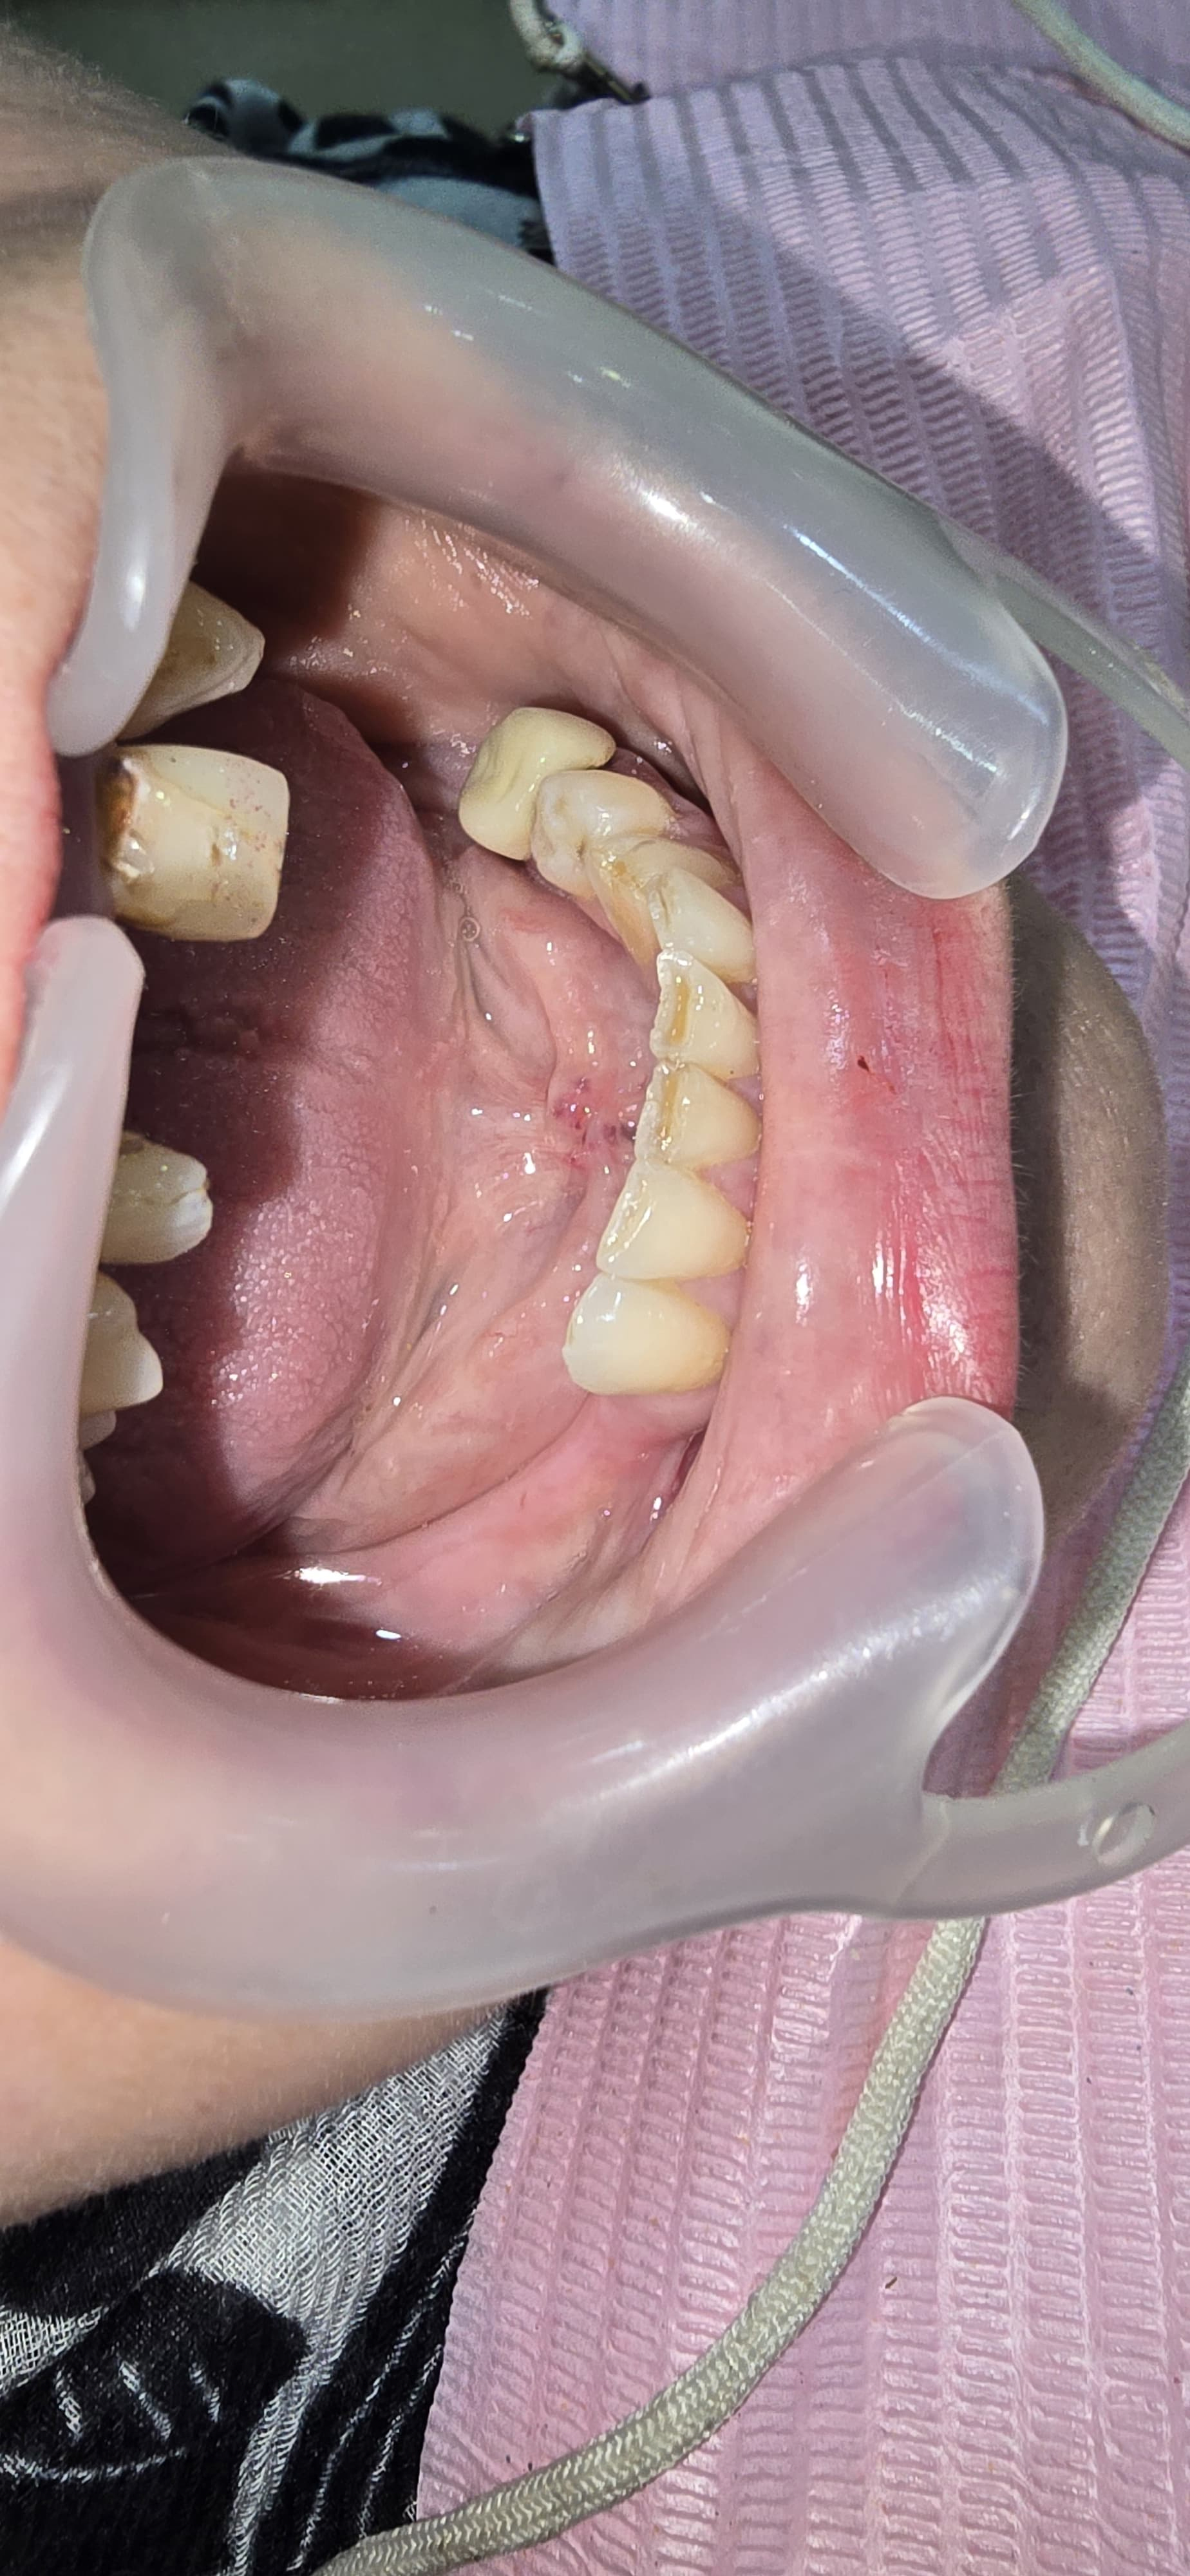

Anterior Implants